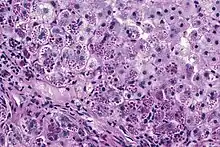

Photomicrograph of a liver biopsy from a patient with alpha-1 antitrypsin deficiency. The PAS with diastase stain shows the diastase-resistant pink globules that are characteristic of this disease.

A1AT is produced in the liver, and one of its functions is to protect the lungs from neutrophil elastase, an enzyme that can disrupt connective tissue.[7] Normal blood levels of alpha-1 antitrypsin may vary with analytical method but are typically around 1.0-2.7 g/l.[12] In individuals with PiSS, PiMZ and PiSZ genotypes, blood levels of A1AT are reduced to between 40 and 60% of normal levels; this is usually sufficient to protect the lungs from the effects of elastase in people who do not smoke. However, in individuals with the PiZZ genotype, A1AT levels are less than 15% of normal, and they are likely to develop panlobular emphysema at a young age. Between 10 and 15% of these people will develop liver fibrosis or liver cirrhosis, because the A1AT is not secreted properly and therefore accumulates in the liver.[13] A liver biopsy in such cases will reveal PAS-positive, diastase-resistant granules. Unlike glycogen and other mucins which are diastase sensitive (i.e., diastase treatment disables PAS staining), A1AT deficient hepatocytes will stain with PAS even after diastase treatment - a state thus referred to as "diastase resistant".